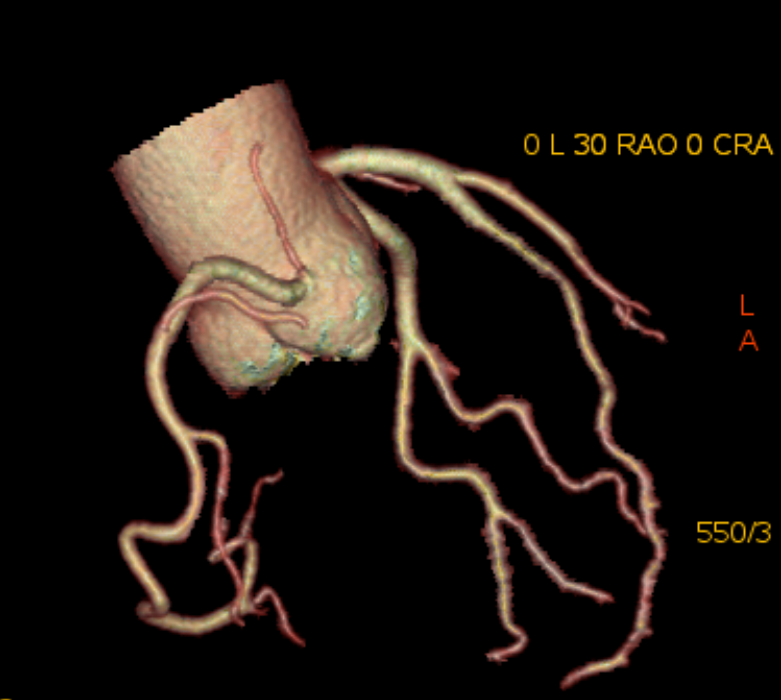

6、心臟CTA、MRI成像技術(shù);

6、心臟CTA是經(jīng)靜脈注射造影劑后進(jìn)行CT快速掃描和圖像重建技術(shù)獲得冠狀動(dòng)脈圖像,以精準(zhǔn)了解冠狀動(dòng)脈是否存在解剖變異、畸形、心肌橋、狹窄,評(píng)估冠狀動(dòng)脈支架或搭橋術(shù)后血管情況等。心臟磁共振檢查具有無(wú)輻射、多參數(shù)、多平面、多序列成像等特點(diǎn),具有良好軟組織分辨力,一次檢查可獲得心臟解剖形態(tài)、心臟功能、血流、心肌灌注或活性、心臟代謝、大血管和冠狀動(dòng)脈的信息,在診斷心肌病方面具有重要意義。

心臟冠脈成像 VR